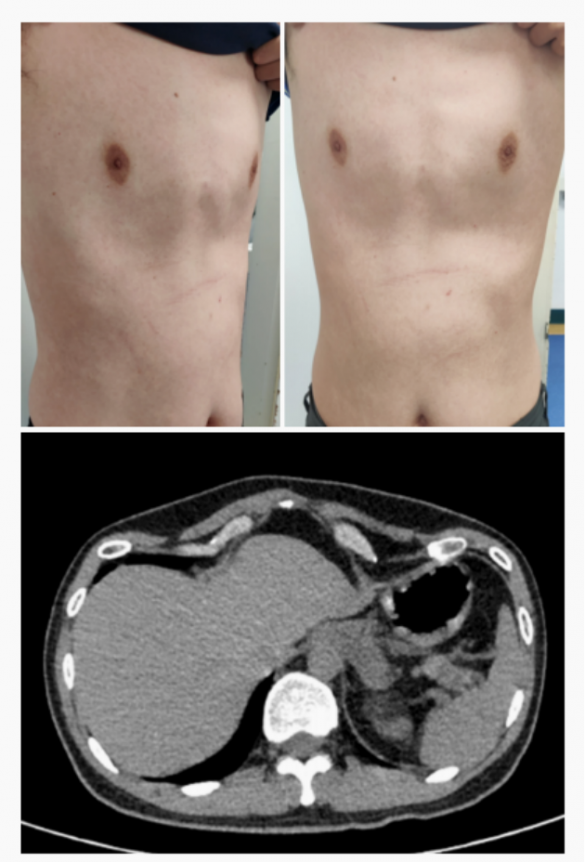

Saddle chest is a unique chest wall deformity characterized by symmetrical indentations on each side of the lower chest. These indentations are not connected and are separated by the normal height of the chest wall in the center, creating the appearance of a “saddle”. This condition, first named by Dr Wenlin Wang, is distinct from other chest deformities, requiring a thorough understanding for proper diagnosis and treatment.

Secondary saddle chest can develop after the Nuss procedure, a surgery typically used to treat pectus excavatum (a condition of an indented chest wall). While the Nuss procedure is highly effective for pectus excavatum, one potential complication is the formation of a saddle chest. The fundamental reason Nuss procedure leads to secondary saddle chest lies in its surgical principle. The Nuss procedure requires using steel bars to elevate the central depression, and the bars need appropriate support points. When the depression is excessively severe—meaning the bar bears excessive force—this force concentrates on the local ribs. If the ribs are sufficiently rigid, it typically won’t cause localized abnormalities. However, if the ribs lack sufficient stiffness, it can lead to localized depressions, resulting in the characteristic saddle chest deformity with bilateral depressions and a normally contoured central region.